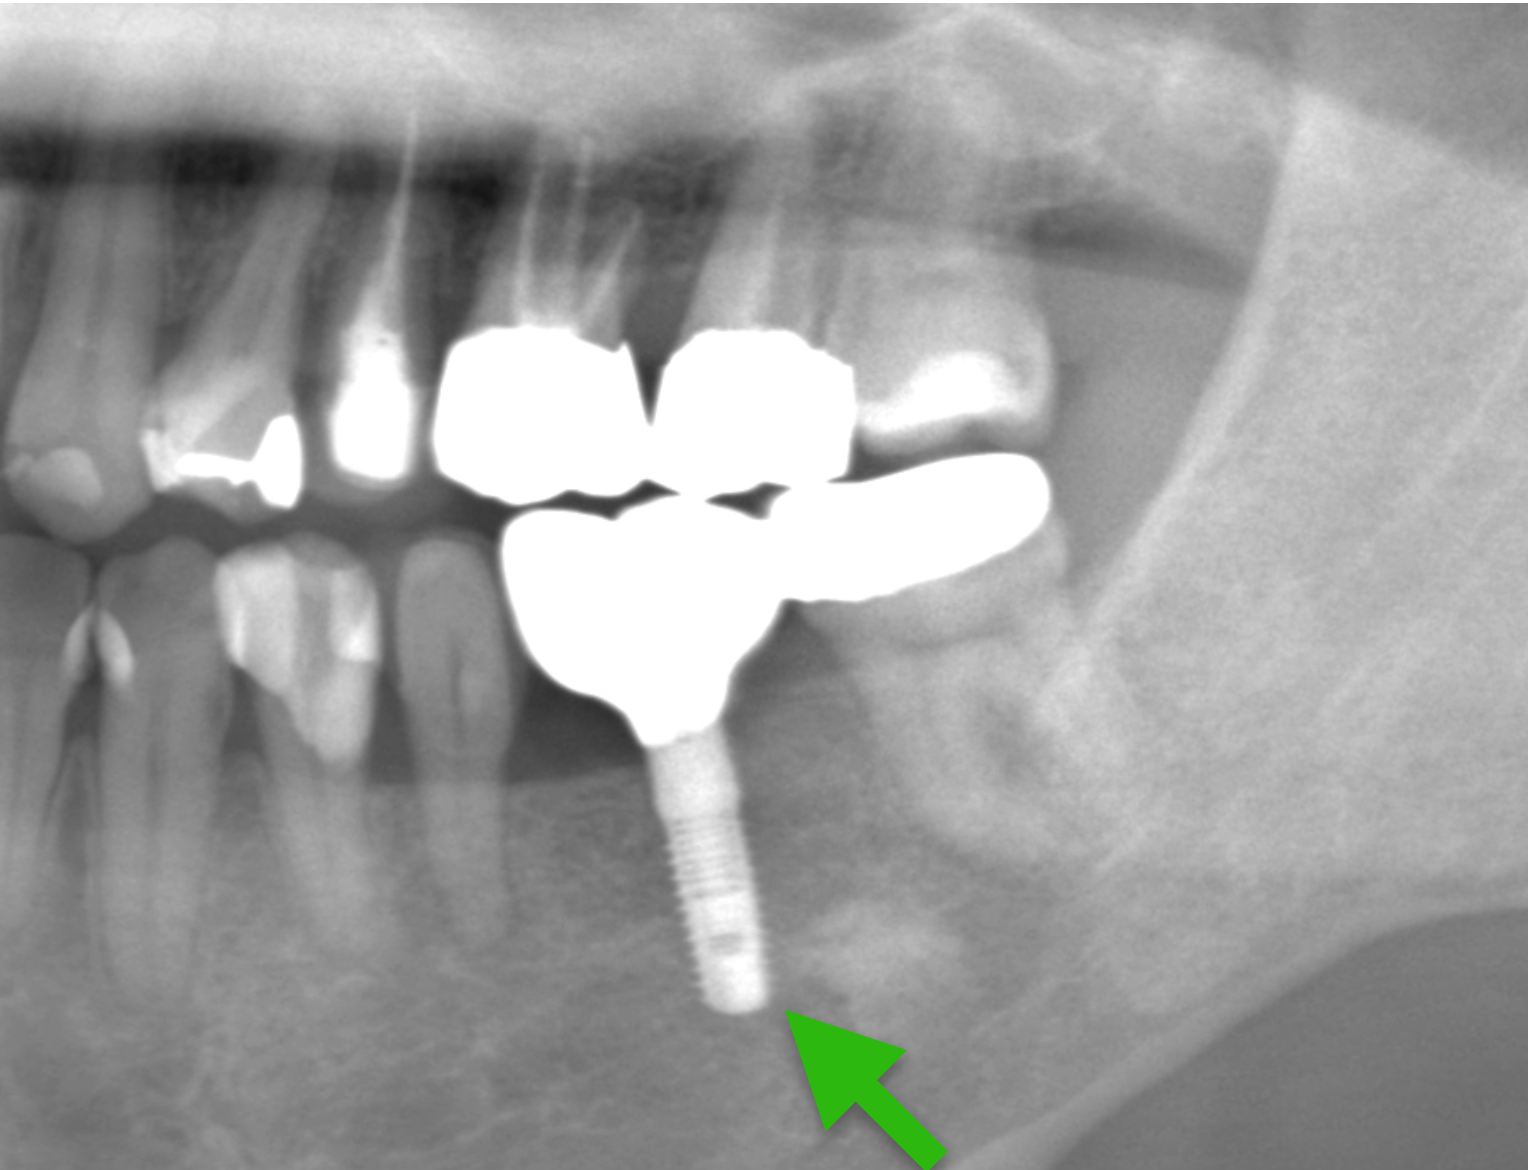

Case8.

![]() |

|---|

| 主 訴 | 歯が取れた |

|---|---|

| 治療期間 | 約4ヶ月 |

| 治療費 | 合計517,000円(税込) |

| 治療内容 | 治療1回目 保存不可能な歯の抜歯 治療2回目 CT撮影にて顎の骨にインプラントが入ることを確認し、サージカルガイドの型取り 治療3回目 ソケットリフトで骨を増やしインプラントを入れる治療 治療4回目 縫合してある糸をとり、周りをクリーニング 治療5回目 インプラントに土台を立てる治療 治療6回目 上部構造(被せ物)の型取り 治療7回目 上部構造(被せ物)をセット |

| 治療のリスク | インプラントの手術の後は腫れ、 痛みが出ることがあります。 インプラントの上部構造は稀に緩むことがあります。 ソケットリフトの後は鼻に違和感がでる場合があります。 |